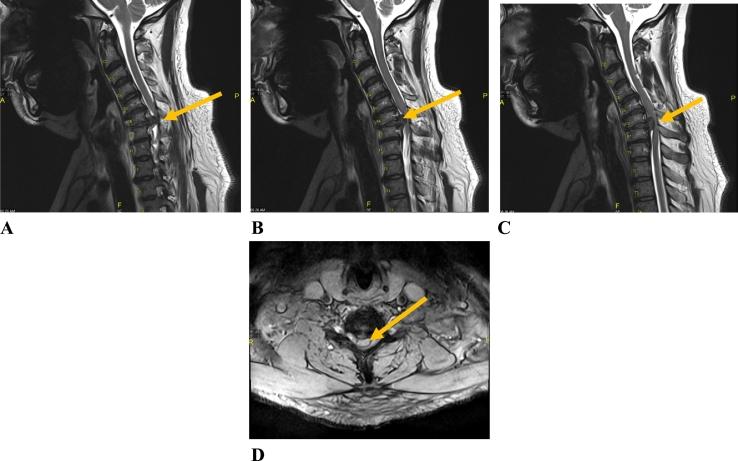

CASE PRESENTATION

A 55-year-old male presenting with neck pain, right and left arms radicular pain and numbness, and unilateral right foot drop following cervical disc prolapse. The patient presented with upper motor neuron lesion signs. MRI showed cervical disc prolapse at two levels, confirming central cause of foot drop. The patient underwent anterior cervical decompression and fusion surgery.

病例报告

一名55岁男性,因颈椎间盘突出症出现颈部疼痛、双侧手臂放射性疼痛和麻木,以及单侧右足下垂。患者表现出上运动神经元损伤体征。磁共振成像显示两个节段的颈椎间盘突出,证实了足下垂的中枢性病因。该患者接受了颈椎前路减压融合手术。